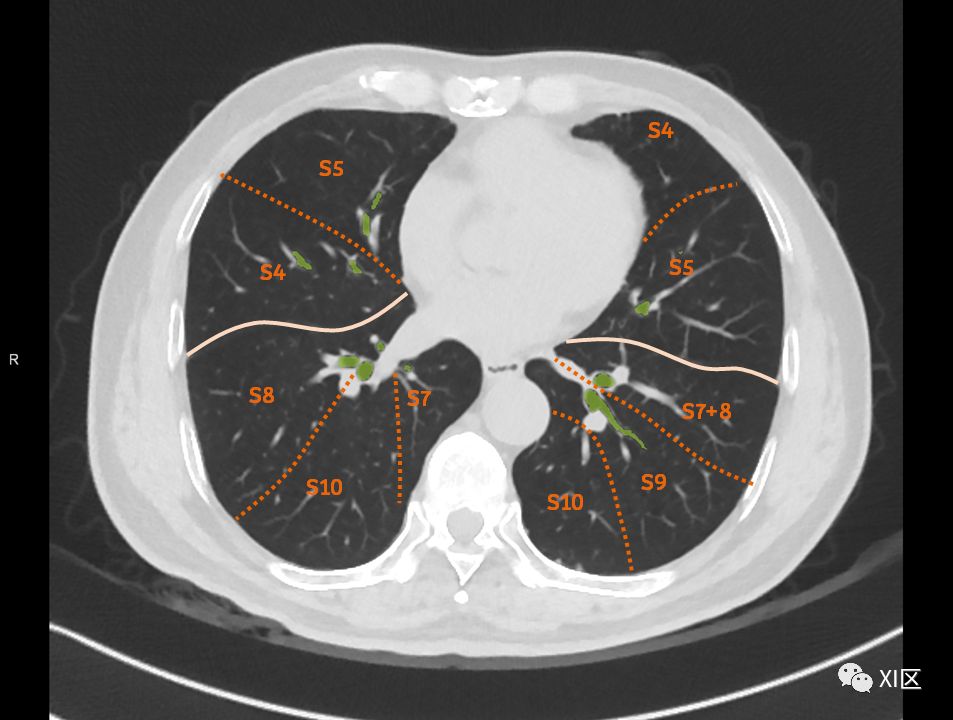

肺的断层分段示意图 医学百科网 | YxBaike.Com

在进行肺的分段时,可以上下观察浏览,沿着相应气管的走形可以更容易准确地进行分段。